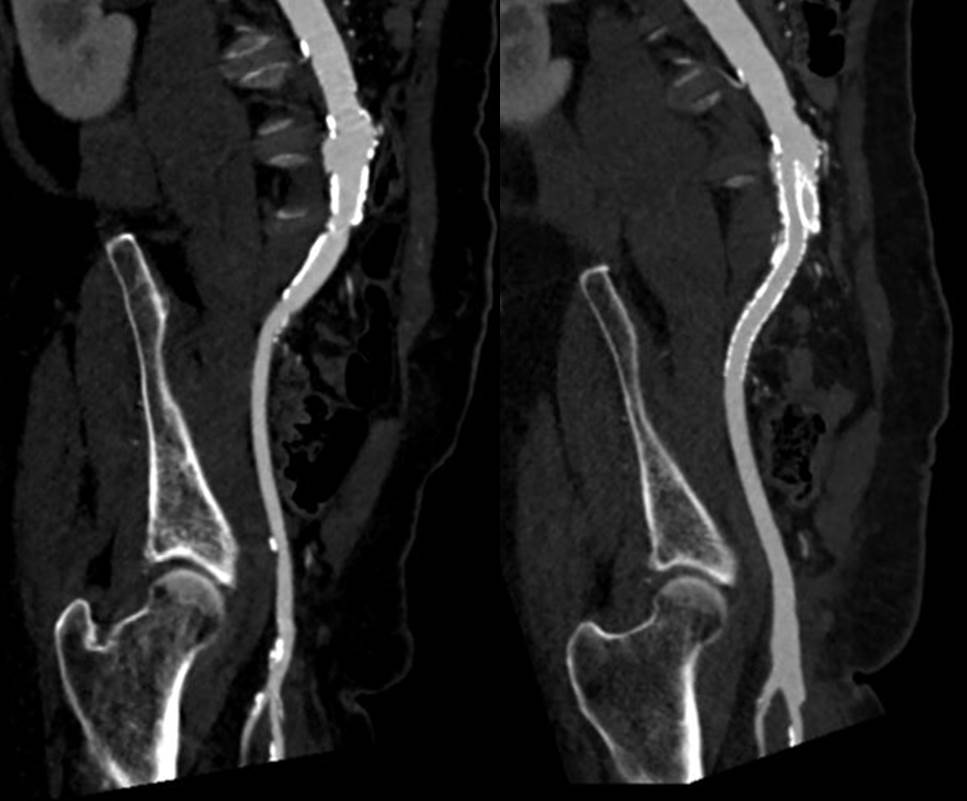

The plaque is extracted and re-establishes patency of the EIA.

The plaque end point is typically treated with a stent -in this case, the common iliac plaque was also treated.

What is nice about this approach is that this artery has been restored to nearly its original condition. I have taken biopsies of the artery several months after the procedure in the process of using the artery as inflow for a cross femoral bypass, and the artery clamped and sewed like a normal artery and the pathology returned normal artery.

This has several advantages over conduit creation which can be a morbid and high risk procedure in patients who require minimally invasive approach. A graft is avoided. The artery is over 8mm in diameter where with stenting up to 8mm with an occlusive plaque, the danger of rupture is present, and often ballooning is restricted to 6mm-7mm. This is insufficient for many TEVAR grafts and TAVR valves.